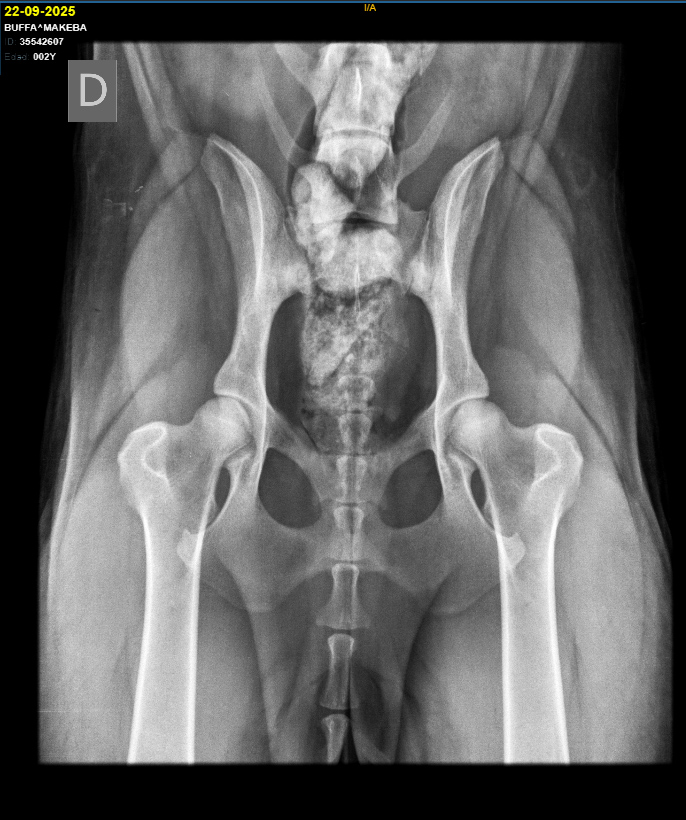

Sex: Female

Fecha de nacimiento: 01/08/2023

Coat: Long

Hips and elbows:

HD A/A ED 0/0

MDR1 +/+ DM N/N

Height: 63cm

Weight: 38kg

Makeba is named in honor of Miriam Makeba, South African singer, global icon of the fight for human rights.

She is the reflection of her father Rixon, a strong, robust but feminine female... with a very even-tempered character, self-confident, sociable and affectionate with everyone, calm but mischievous when no one is looking. Despite her remarkable size, she is very subtle and gentle in her manner, and has a very unusual wisdom in a young dog.